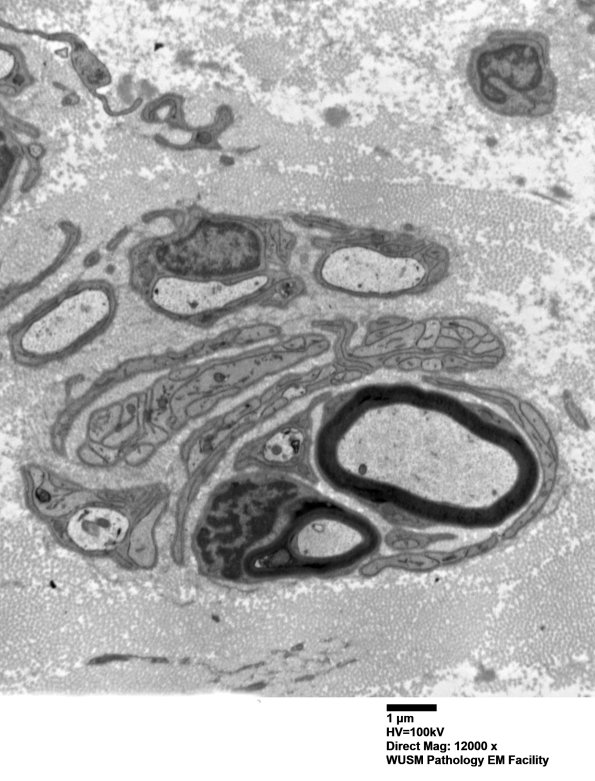

Forms of POB in which residual myelinated axons persist without demyelinated forms or remyelinated elements. These elements represent collections of Schwann processes with residual axons and bands of Büngner. There is residual axon and myelin debris in Schwann cells but no actively degenerating axons or ongoing demyelination. (electron micrograph)